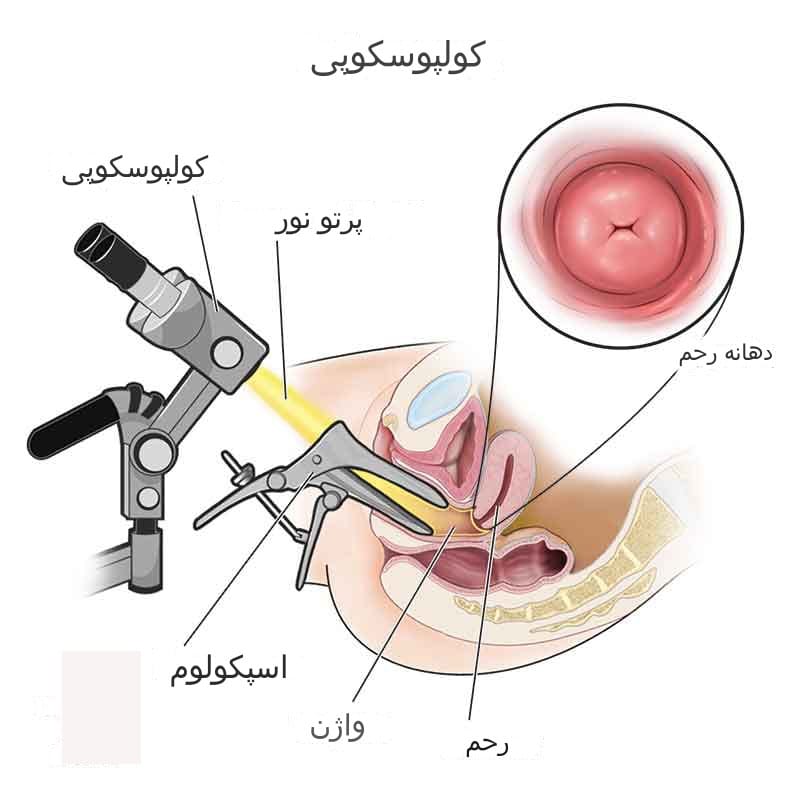

کولپوسکوپی روشی برای مشاهده دهانه رحم، واژن و ولوو یا فرج از طریق یک دستگاه بزرگنمایی خاص به نام کولپوسکوپ است. کولپوسکوپ می تواند نمای طبیعی را تا حد زیادی بزرگ کند. این معاینه به یک متخصص زنان و زایمان اجازه می دهد تا مشکلاتی که تنها با چشم غیر مسلح قابل مشاهده نیستند را پیدا کند.

نحوه انجام کولپوسکوپی به اینصورت است که مانند معاینه لگن، شما روی تخت معاینه زنان یا تخت ژنیکولوژی به پشت دراز می کشید و پاهای خود را بر روی قسمت مربوط به پا که بالاتر قرار دارد و پاها را حمایت میکند قرار میدهید، سپس پزشک متخصص زنان شما از اسپکولوم برای جدا کردن دیواره های واژن استفاده می کند تا داخل واژن و دهانه رحم دیده شود. یک نور روشن هم جهت مشاهده دقیق تر به ناحیه تابیده می شود. دستگاه کولپوسکوپ درست خارج از ولوو یا فرج قرار می گیرد، منظور این است که این دستگاه وارد واژن شما نمی شود بلکه با باز شدن واژن از طریق اسپکولوم، به حفره واژن و دهانه رحم یعنی سرویکس شما از بیرون نگاه میکند و با دید میکروسکوپی از طریق لنزهایی که دارد تصویری با بزرگنمایی زیاد از این نواحی در اختیار پزشک متخصص زنان قرار میدهد تا تغییراتی که با چشم غیر مسلح قابل دیدن نیستند را ببیند.

پزشک متخصص زنان وزایمان شما (دکتر زنان) از عدسی کولپوسکوپ نگاه می کند. کولپوسکوپ دید را بزرگ می کند و نوری را به فرج، واژن و دهانه رحم می تاباند.